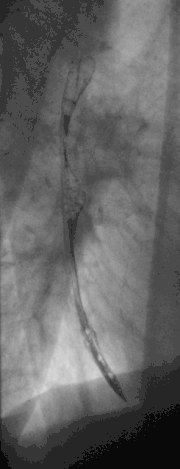

Masa esofágica media